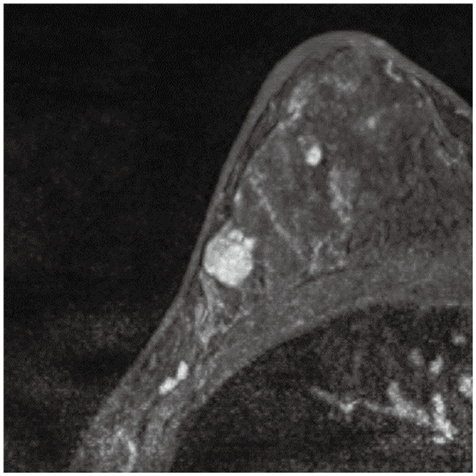

症例1

症例1の患者情報

50歳代,女性。

左乳房腫瘤を自覚,精査のために乳房造影MRIを撮像した。